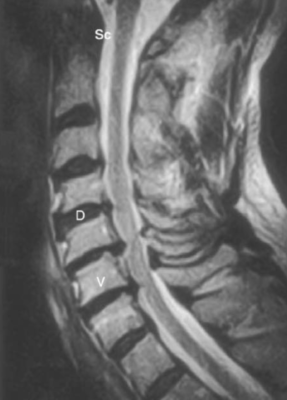

LIÊN HỆ HÌNH ẢNH HỌC

Cột sống cổ

Các chữ viết tắt:

- V = Vertebral body; thân đốt sống

- D = Intervertebral disc; đĩa gian sống

- Sc = Spinal cord; tuỷ sống

- S = Spinous process; mỏm gai

- N = Neural foramen; lỗ thần kinh

- P = Pedicle of vertebral arch; cuống cung

- I = Intervertebral disc space; khoảng đĩa đệm

- F = Facet joints; khớp diện nhỏ/facet

- T = T1 transverse process; mỏm ngang T1

Cột sống thắt lưng